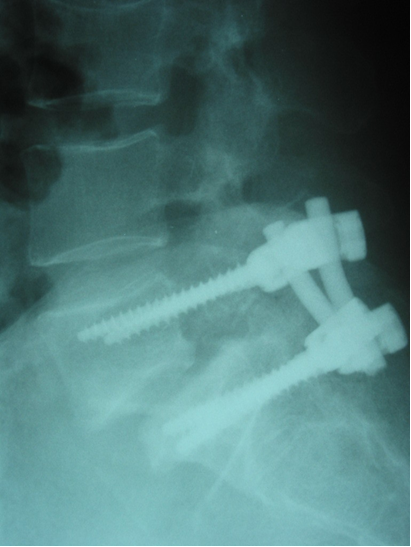

Spondiloliza pomeni prekinitev kostne zveznosti v pars interarticularis vretenca. Nikoli se ne pojavlja pri novorojenčkih in otrocih, preden ne shodijo. Incidenca spondilolize pri 2- do 6-letnih otrocih znaša 3 odstotke, pri 5- do 7-letnikih je enaka kot pri odraslih (6 odstotkov), pri športnikih pa se giblje med 15 in 20 odstotki. Večina defektov prizadene peto ledveno vretence (90 odstotkov). V višjem odstotku srečamo to bolezensko stanje pri športnikih, ki izvajajo ponavljajoče se hiperekstenzijske aktivnosti, na primer pri potapljačih (63 odstotkov), gimnastikih (33 odstotkov) in napadalcih rugbyja (33 odstotkov). Kombinacija ponavljajočih se osnih preobremenitev v iztegnjenem položaju hrbtenice lahko postopoma povzroči zlom zaradi utrujenosti materiala (kostnine) v predelu pars, spondilolizo ima 36 odstotkov dvigalcev uteži. Pri nekaterih bolnikih se postopoma pojavi spondilolisteza, tj. zdrs višjega vretenca navzpred glede na nižjega. V večini primerov bolniki ne čutijo večjih težav, dolgotrajna bolečina se pojavi pri okoli 13 odstotkih bolnikov. Običajno tožijo o bolečini v križu, ki se poveča ob aktivnostih. Pri hoji so okornejši in hodijo s krajšimi koraki zaradi spazma upogibalk kolena. V primerih izrazitejše spondilolisteze tipamo med trnastima izrastkoma zamaknjenih vretenc bolečo stopničko. Pogosta je koreninska okvara pete ledvene korenine, ki je utesnjena v svojem poteku pod vnetim in zadebeljenim tkivom v predelu pars interarticularis. Pri diagnostiki si pomagamo z nativnimi rentgenskimi posnetki, ki jih dopolnimo še s polstranskimi in funkcionalnimi posnetki za dokaz defekta v pars (ovratnica terierja) oziroma nestabilnosti. Za natančnejšo opredelitev opravimo še kostno scintigrafijo, računalniško tomografijo (CT) in magnetnoresonančno tomografijo. Skeletno nezrele bolnike, pri katerih radiološko in/ali scintigrafsko odkrijemo svežo ali aktivno okvaro, zdravimo z imobilizacijo. Največkrat uporabljamo torakolumbosakralni mavčev steznik, ki ga bolniki zamenjajo v štiri- do šesttedenskih presledkih, sicer pa ga nosijo tri do štiri mesece. Steznik, predelan na odvzem, bolniki nato postopoma opuščajo. Imobilizaciji sledi nekaj mesecev trajajoča rehabilitacija, med katero krepimo mišičje trupa in medenice ter vzdržujemo kardiorespiratorno zmogljivost. Če bolečina ne popusti ali se pri športni aktivnosti ponovno pojavi, svetujemo trajno spremembo aktivnosti ali operativno zatrditev defekta. V primeru spondilolisteze sanacija defekta brez kirurškega zdravljenja ni več mogoča. V fazi bolečin omejimo telesno aktivnost in pričnemo z razteznimi vajami za upogibalke kolena. Ko se bolečina umiri, dodamo vaje za krepitev mišičja trupa in medeničnega obroča. Športno aktivnost dovolimo, kadar zdrs ne presega 50 odstotkov širine telesa vretenca in bolniki nimajo znakov koreninskega draženja. Mladostnike radiološko kontroliramo v šest- do dvanajstmesečnih presledkih. Operativno zatrditev (fuzijo »in situ«) svetujemo, kadar je bolečina prisotna kljub zdravljenju več kot šest mesecev, kadar zdrs napreduje in kadar se pojavijo nevrološki izpadi. V primerih, ko zdrs presega 50 odstotkov širine telesa vretenca, svetujemo skeletno nezrelim bolnikom zatrditev z redukcijo zdrsa ob sočasni sprostitvi živčevja, kadar so prisotni nevrološki izpadi. Najustreznejše zdravljenje za simptomatske skeletno zrele bolnike s težjo stopnjo spondilolisteze in degeneracijo medvretenčnega diska je prav tako zatrditev prizadetega vertebrodinamičnega segmenta. Opisane so številne operativne tehnike, dobre izkušnje imamo s kombinirano posterolateralno in medtelesno zatrditvijo s presadkom mečnice ob uporabi transpedikularnega notranjega fiksatorja (slika 2).

Slika 2. Stranski rentgenski posnetek stanja po operacijskem zdravljenju spondilolitične spondilolisteze petega ledvenega vretenca. S puščico je označen presadek mečnice po medtelesni zatrditvi in učvrstitvi s transpedikularnim notranjim fiksatorjem.